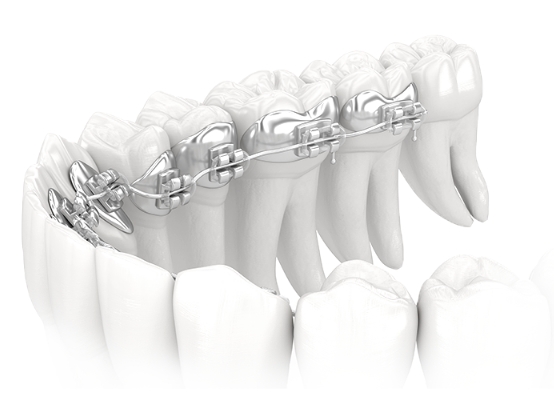

• 금속교정

기본에 충실한 금속교정

교정 치료는 많은 지식과 의술 뿐 아니라

의료진의 정성과 관심 또한 중요합니다.

순천미르치과의원은 치과교정전문의를 비롯한

의료진 모두 환자분과

충분히 감정을 교류하고

대화하며 함께 동행하는 치료를 합니다.

금속교정